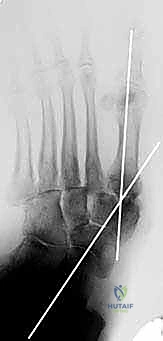

2. الأشعة السينية الحاملة للوزن (Weight-bearing X-rays): لتقييم الانهيار العظمي.

هذه هي الخطوة الأكثر دقة. يقوم الدكتور هطيف بإعادة العظام إلى وضعها التشريحي الطبيعي لاستعادة القوس الطولي للقدم، والتأكد من أن باطن القدم أصبح مسطحاً وقابلاً لتحمل الوزن مستقبلاً دون التسبب في تقرحات.